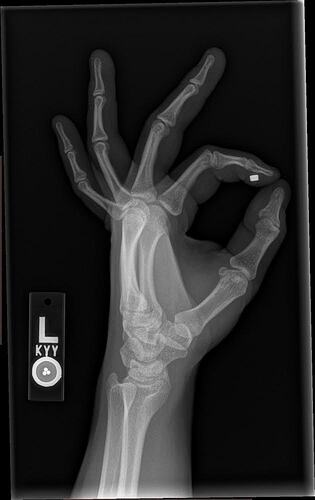

Little Titan update: approaching 2 years with it in and no complaints so far. Nothing strange has happened with it. I’ve bumped it causing significant pain two or three times over the years but I’d compare them to a bad toe stubbing. Painful for a minute, then sore fore less than a day. I can say the sensitivity has slightly decreased since the first 6 months but I suspect my healing tissue was just more sensitive than current tissue. I can still feel the magnets in the airood case in my left pocket as my hand swings by my leg while I walk (that’s one of my favorite things). Here are some x-rays I got this year of both my titan and my NExT installs. NExT chip was installed by a nurse I know Thanksgiving of 2022. No numbing, but the back of the hand wasn’t a very painful place and it went smooth and well.